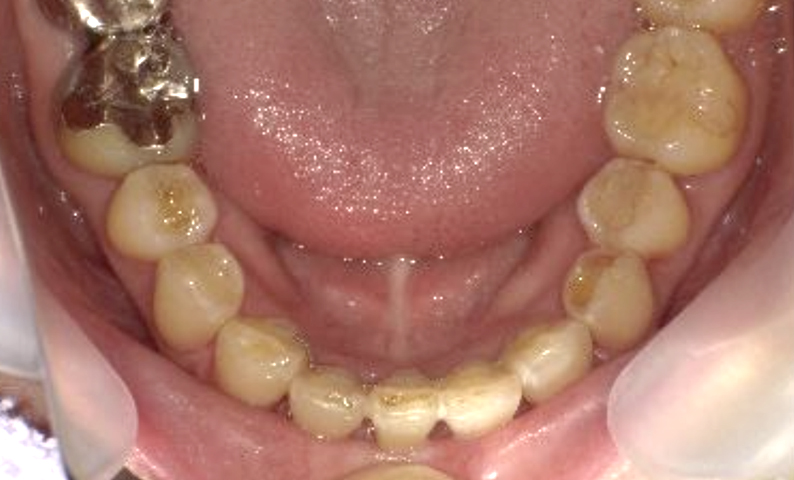

症例_002 上顎だけの部分矯正

治療期間:7ヶ月金額:30万円+税女性前歯のガタガタ上の前歯だけ

| Before | After |

|---|---|

|